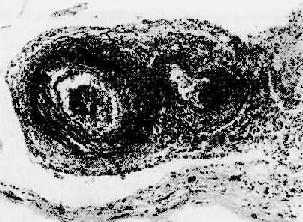

图4-12 红斑性狼疮之脾病变 脾小体中央细动脉壁呈洋葱皮样结构 (7)淋巴结:全身淋巴结均有不同程度的肿大,窦内皮增生。其中较多的浆细胞,小血管变化与脾所见相同。 2.口眼干燥综合征 口眼干燥综合症(Sjǒgren syndrome)临床上表现为眼干、口干等特征,乃唾液腺、泪腺受免疫损伤所致。本病可单独存在,也可与其他自身免疫病同时存在,后者最常见的是类风湿性关节炎、SLE等。病变主要累及唾液腺及泪腺,其他外分泌腺包括呼吸道、消化道腺体也可受累。 唾液腺的组织学病变主要表现为腺管周围大量炎细胞浸润,主要是淋巴细胞和浆细胞,有时可形成淋巴滤泡并有生发中心形成。伴腺管上皮增生,引起管腔阻塞。病变晚期腺泡萎缩、纤维化,为脂肪组织所替代。个别病例浸润的淋巴细胞形成淋巴瘤样结构。由于唾液腺的破坏而引起口腔粘膜干裂及溃疡形成。 泪腺的类似病变可导致角膜上皮干燥、炎症及溃疡形成。呼吸道、消化道受累可导致相应的鼻炎、喉炎、支气管炎、肺炎及萎缩性胃炎。在肾可发生间质性肾炎,肾小管周围大量单个核细胞浸润,导致肾小管萎缩、纤维化,因肾小管功能损害而引起肾小管性酸中毒、磷酸盐尿等颇常见。 淋巴结肿大并有增生性变化,核分裂多,故又名假性淋巴瘤。值得提出的是本病患者发生恶生淋巴瘤的机会较正常人高40倍。 发病机制 本病的发病机制尚不清楚。由于常伴发SLE和类风湿性关节炎,提示本病的发生与免疫性损伤有关。患者B细胞功能过度,表现为多克隆高球蛋白血症和类风湿因子(RF)、抗核抗体、冷球蛋白及抗唾液腺抗体的形成。近年来并发现两种特征性抗核糖核蛋白成分的自身抗体,分别命名为抗SS-B和SS-A,在本病有很高的阳性率(60%、70%),对本病的诊断有参考价值。病灶处有大量B及T细胞浸润,后者大部分为T辅助细胞,也有一部分为T杀伤细胞,提示亦有细胞免疫机制的参与。 3.类风湿性关节炎 详见骨关节疾病章。 4.硬皮病 硬皮病(scleroderma)又名进行性系统性硬化症(progressive systemic sclerosis),以全身许多器官间质过度纤维化为其特征。95%以上的患者均有皮肤受累的表现;但横纹肌及许多器官(消化道、肺、肾、心等)受累是本病主要损害所在,病变严重者可导致器官功能衰竭,威胁生命。 病因和发病机制本病病因不明,其发病可能与以下因素有关: (1)胶原合成增加:体外培养证实,患者纤维母细胞合成胶原的能力明显高于正常人,合成超过降解,导致大量胶原纤维的积集; (2)Ⅳ型变态反应:在皮肤病变中有T细胞浸润,所分泌的淋巴因子及其刺激巨噬细胞分泌的因子可刺激纤维母细胞大量合成胶原; (3)自身抗体:50%患者有轻度高丙种球蛋白血症及多种自身抗体,包括RF,抗平滑肌抗体,抗核抗体等,可能由于抗原抗体免疫复合物的沉积或内皮细胞毒的作用,造成小血管内皮细胞损伤、血栓形成、管壁纤维化、管腔狭窄,导致组织缺氧而引起纤维间质增生。 【病变】 (1)皮肤:病变由指端开始,向心性发展,累及前臂、肩、颈、脸,使关节活动受限。早期受累的皮肤发生水肿,质韧。镜下,主要表现为小血管周围淋巴细胞浸润,毛细血管内皮细胞肿胀、基膜增厚、管腔部分阻塞,间质水肿,胶原纤维肿胀,嗜酸性增强。随着病变的发展,真皮中胶原纤维明显增加,并与皮下组织紧密结合,表皮萎缩变平,黑色素增加,钉突和附属器萎缩消失,小血管增厚、玻璃样变。晚期手指细而呈爪状、关节活动受限,有时指端坏死甚或脱落,面部无表情呈假面具状。 (2)消化道:约有1/2患者消化道受累,粘膜上皮萎缩,固有层、粘膜下层、肌层为大量胶原纤维所取代,血管周单个核细胞浸润。病变以食管下2/3段最严重,管腔狭窄,缺乏弹性。小肠、结肠也可受累。临床上出现吞咽困难、消化不良等症状。 (3)肾:叶间小动脉病变最为突出,表现为内膜粘液样变性,伴内皮细胞增生及随后的管壁纤维化、管腔明显狭窄,部分病例并有细动脉纤维素样坏死。临床上可出现高血压,与恶性高血压肾病变难以区别。约50%患者死于肾功能衰竭。 (4)肺:弥漫性间质纤维化,肺泡扩张、胞泡隔断裂,形成囊样空腔,本病是造成蜂窝肺的重要原因之一。 5.结节性多动脉炎 结节性多动脉炎(polyarteritis nodosa)是全身动脉系统的疾病,表现为中小动脉壁的坏死性炎症。患者以青年人为多,有时也可发生在儿童及老人、男女之比为2~3:1。 病变各系统或器官的中小动脉均可受累,其中以肾(85%)、心(75%)、肝(65%)、消化道(50%)最为常见。此外,胰、睾丸、骨骼肌、神经系统和皮肤也可受累。 病变多呈节段性,以血管分叉处最为常见。内眼观,病灶处形成直径约2~4mm的灰白色小结节,结节之间的血管壁外观正常。镜下,急性期表现为急性坏死炎症,病变从内膜和中膜内层开始,扩展至管壁全层及外膜周围,纤维素样坏死颇为显著,伴炎细胞浸润(图4-13)尤以嗜酸性及中性粒细胞为多,继而有血栓形成。以后的进展是纤维增生,管壁呈结节性增厚,管腔机化阻塞和明显的动脉周围纤维化。值得注意的是早期炎性坏死变化及后期胶原化可同时存在。病变的主要后果是缺血性损害和梗死形成。